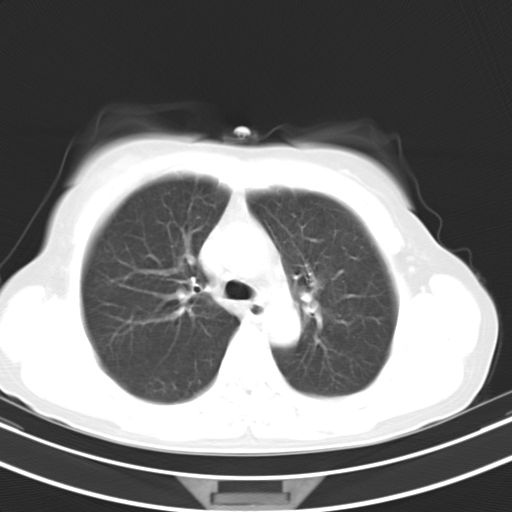

右肺上叶前段积左肺舌叶炎症,建议严格抗炎后2周复查!

右肺上叶尖后段班片影不能出外肺结核。左肺舌叶三角形实变影,增强明显。考虑炎性病变

右肺为炎性改变,左肺病灶影像所见1、楔状实变影,边缘呈刀切样,见支气管气象,2、近端纹理影增重。

两肺病变考虑炎症可能性大。(左肺病变呈楔状实变影,有支气管气象,近端纹理影增重)。

1)右肺上叶前段及左肺上叶舌段感染性病变;建议抗炎治疗后复查。2)左侧少量胸腔积液。

考虑右肺上叶前段及左肺舌叶炎症,建议抗炎治疗后复查除外结核。